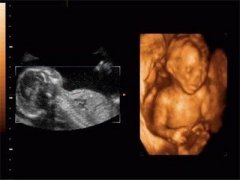

在孕22-26周,产检医生就会提醒准妈去做一个畸形筛查!这也是妈妈第一次见到宝宝的...[详情]